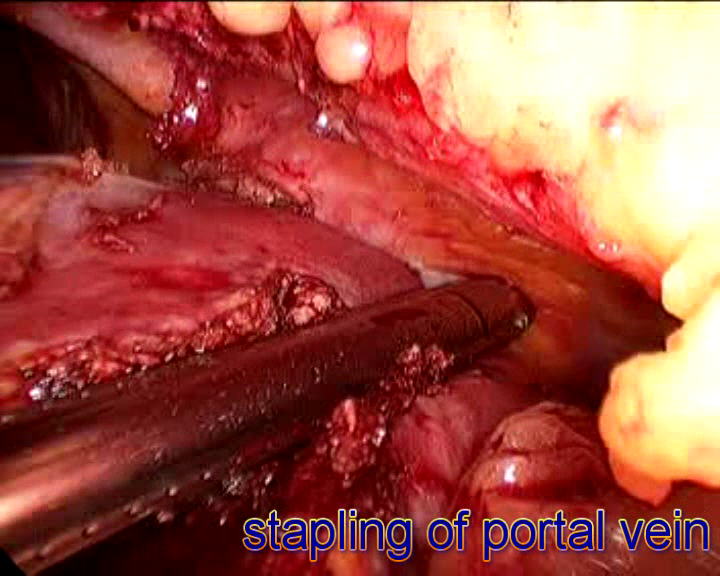

Laparoscopic Liver, Pancreas and Bilary Surgery

are advanced surgical procedures that requires adequate training in traditional open surgery as well as proficiency in laparoscopic techniques. Relevant and adequate training in step-wise manner up the ladder of complexity should be acquired by surgeons offering this approach coupled with adoption of modern instrumentation and equipment to ensure safe execution of the surgical procedures.

- Liver resection (for cancer and other liver tumor)